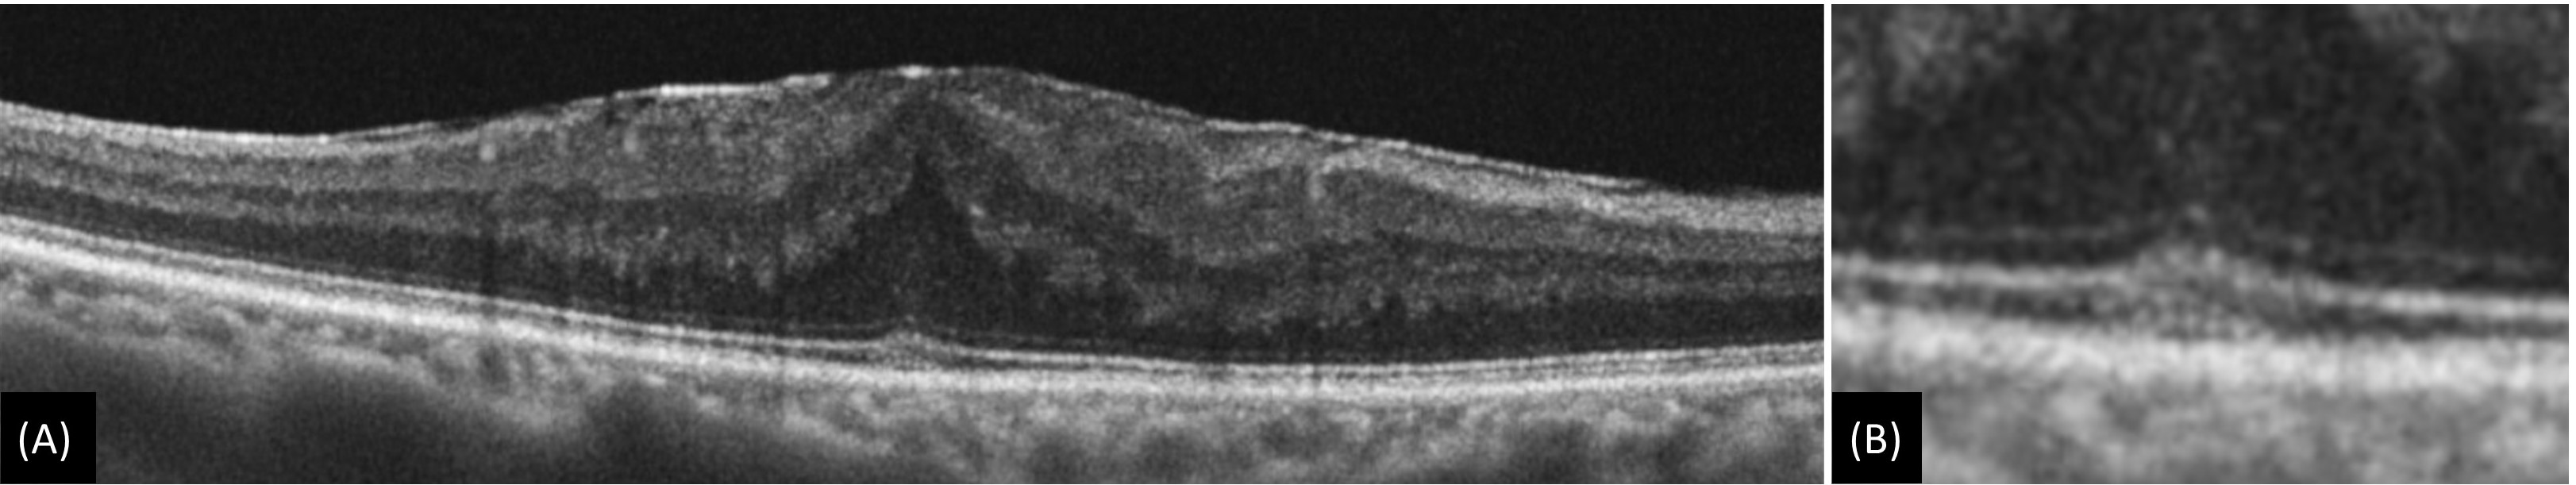

Figure 5: (A) Epiretinal membrane with acquired vitelliform lesion which is characterized by presence of thick dome-shaped subfoveal hyperreflective material between ellipsoid zone and retinal pigment epithelium. (B) Magnified image